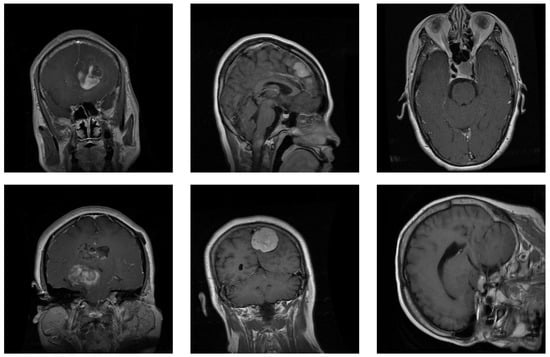

Figure 1 depicts several examples of brain tumors in the dataset. This dataset forms part of a larger collection that encompasses eight distinct cancer types from different organs: acute lymphoblastic leukemia, brain, breast, cervical, kidney, lung, colon, and oral cancer. The images are in JPEG format with dimensions of  pixels. We selected brain cancer, which contained the three previous tumor subclasses. Each subclass included the same number of images (5000 MRIs).

Figure 1.

Samples from the brain dataset: the first column shows two examples of glioma tumors; the middle column shows meningioma tumors; and the last column depicts images of pituitary tumors.